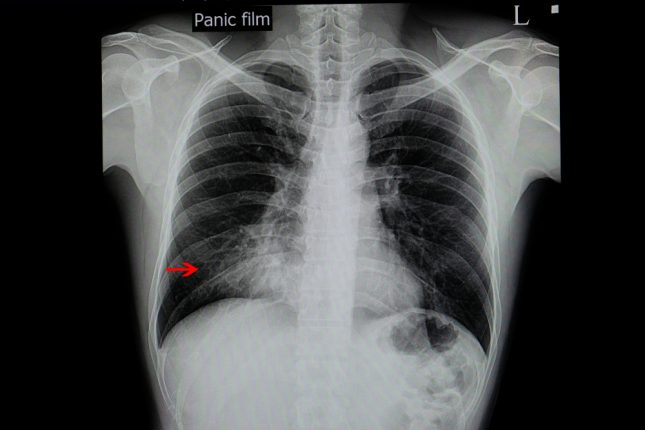

בסקירה נמצא כי חולים עם פנאומיניטיס בדרגה 5 לרוב מפתחים תסמינים מוקדם יותר מאשר אלה עם פנאומיניטיס בדרגות נמוכות יותר. לעתים קרובות התסמינים אינם מגיבים לטיפול בסטרואידים או חוזרים לאחר הפחתת סטרואידים. ממצאי ההדמיה משתרעים הרבה מעבר לאזור שקיבל קרינה במינון הגבוה, כולל נוכחות בריאה הנגדית למקום הגידול. גורמי סיכון תלויי מינון כוללים את הקצוות של ההתפלגות – נפח נמוך משמעותית מהממוצע ונפח גבוה משמעותית מהממוצע.